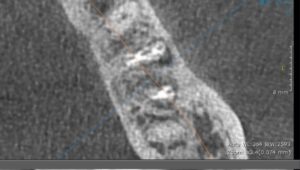

この後CTを再度撮影し、根分岐部の骨再生、歯根尖の骨再生を確認できた。したがって外科的根管治療は行わず、保存治療で完了となった。

【CT画像 根分岐部の骨再生が確認できる】

【黄矢印 根分岐部骨再生部分】

【治療後2年 骨再生が見られる】